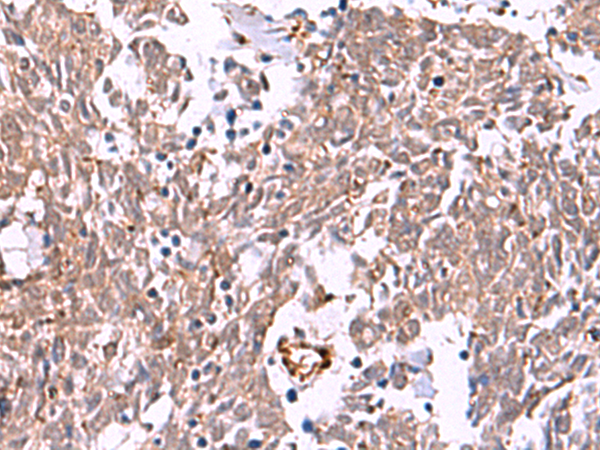

IHC positive control:

Human lung cancer and Human ovarian cancer

IHC Recommend dilution:

40-200